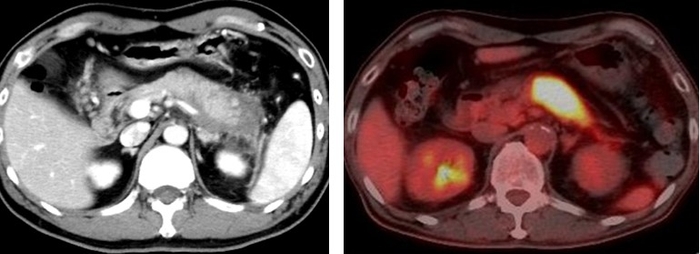

自己免疫性膵炎は、自己の免疫システムが膵臓を攻撃することで発症し、膵臓の腫大に伴い黄疸、腹痛、糖尿病などの症状があらわれる、高齢の男性に多い指定難病です。現在、国内患者数は約1万人と推定されており、年々増加しています。自己免疫性膵炎の大半は、全身性のIgG4関連疾患※5 が膵臓に起こったもので、ステロイドによる免疫制御療法が効果的ですが、さまざまな副作用があり寛解後も長期間の維持療法が必要です。また、約10%の患者は治療を継続しているにもかかわらず再発することが知られており、自己免疫性膵炎の病態の理解に基づいた新規治療法の開発が望まれています。

仮説を検証するため、まず、3種類のAhR活性化分子の投与が、実験的自己免疫性膵炎の発症に及ぼす効果を検討しました。自己免疫疾患モデル動物であるMRL/MpJマウスに、Poly(I:C)(合成二本鎖RNA:ウイルス由来の二本鎖RNAと同等の免疫賦活作用を有する)を繰り返し投与することにより、自己免疫性膵炎を誘導しました。この自己免疫性膵炎モデルマウスに対して、ダイオキシンの一種である2, 3, 7, 8-テトラクロロジベンゾジオキシン、ブロッコリーに多く含まれるインドール系化合物の一つであるIPA(インドール-3-ピルビン酸)、植物由来生薬である青黛の3種類のAhR活性化分子を含む餌を与えました。その結果、3種類全てのAhR活性化分子の投与が、効率良く自己免疫性膵炎の発症を防ぐことを見出しました。

また、自己免疫性膵炎患者でも、ステロイド治療により病気の状態が改善すると、血清中のIL-22が大きく増加することも明らかになり、AhR活性化によるIL-22の増加が、自己免疫膵炎の発症抑制に寄与していることが明らかになりました。

本研究により、自己免疫性膵炎の発症メカニズムの解明や新規治療法の開発への新たな一歩に繋がることが期待されます。現在、近畿大学病院において、自己免疫性膵炎患者を対象として、青黛(試験薬名:青黛腸溶FC錠)を用いた臨床研究(試験ID:jRCTs051210171)を実施しており、青黛の安全性・有効性を確認する予定です。